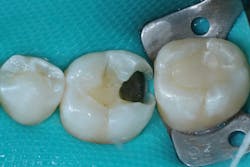

Caries lesions were removed and air abrasion was employed to remove impurities on the unprepared tooth surfaces and create increased surface area for bonding. Preparation of the class II carious lesions revealed demineralization on the adjacent tooth structure (figure 3). When lesions such as these are discovered, dentists are often at a crossroads whether to intervene or monitor the area for progression. It is my experience that these early caries lesions can be predictably arrested with resin infiltration (figure 4), and that no intervention usually results in the progression of caries.

In this case, lateral access was achieved by the preparation of the adjacent teeth as part of the proposed treatment plan. Early caries lesions that are noted on radiographs that are not accessible in cases such as this one can be accessed by placing an orthodontic spacer. This patient was restored with direct composite bonding (figure 5) and these restorations have proven to have a favorable long-term outcome (figure 6).